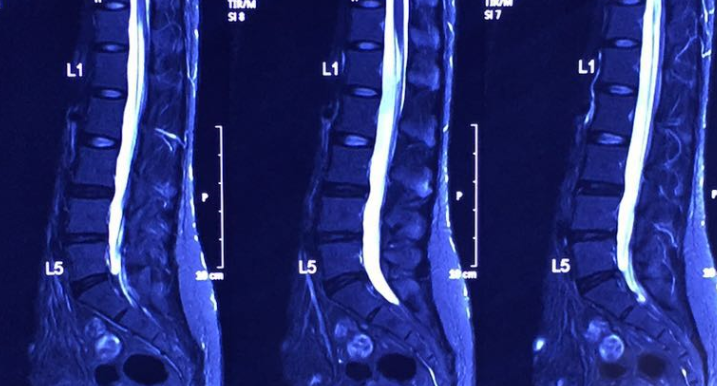

圖說MR 3、MR 4

2016年1月椎間盤突出的程度已大大改善,之前神經根被壓着的部分亦消失。